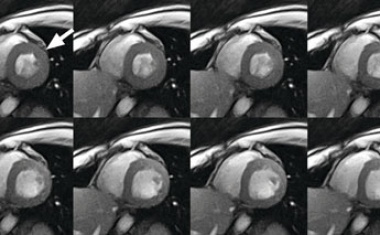

Eine neue MRT-Technik in der Universitätsmedizin Mainz erkennt Schlaganfälle in kürzester Zeit.

Den weltweit ersten Prototypen zur Echtzeit-Verfolgung für bewegliche Tumoren mittels Magnetresonanz-Tomographie (MRT) während der Protonentherapie wollen Forscher*innen des Helmholtz-Zentrums Dresden-Rossendorf (HZDR) aufbauen.